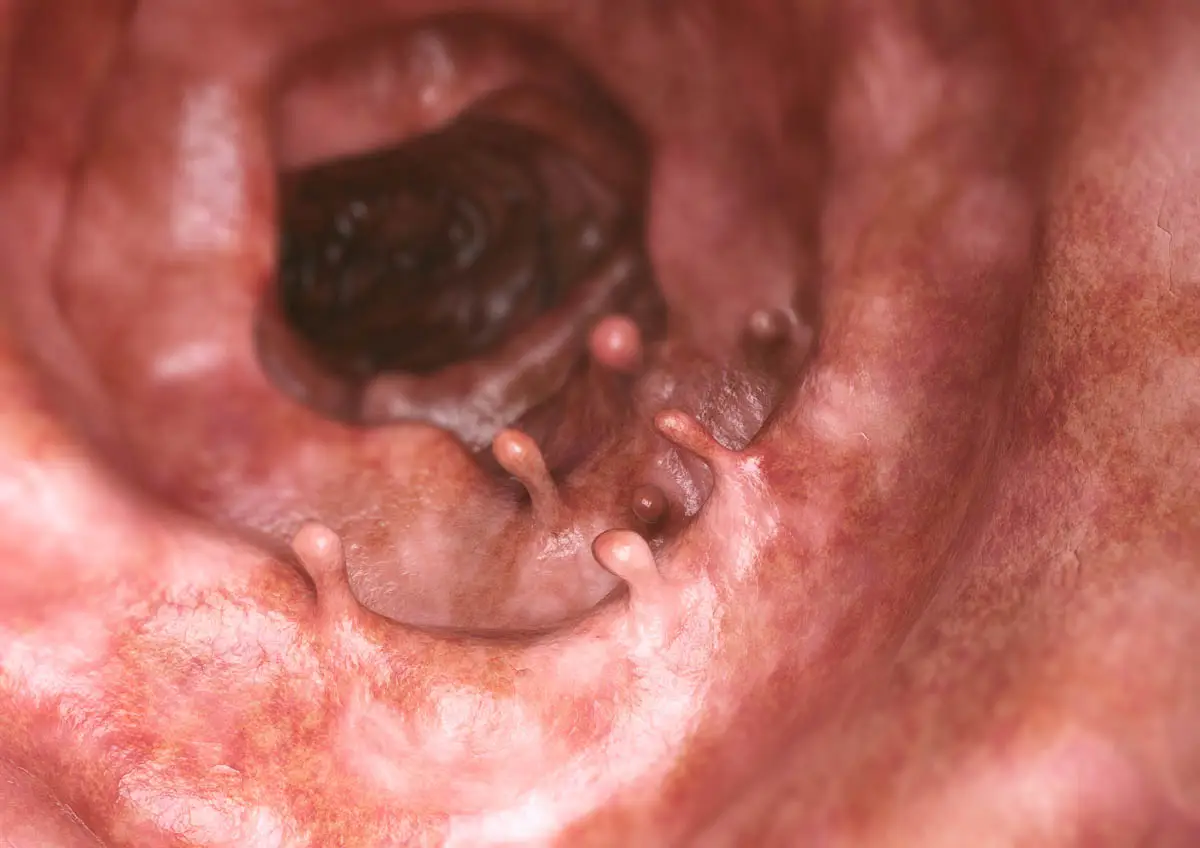

الاورام الحميدة المستقيم

هذه الأنواع من الاورام الحميدة غير عادية في القطط. الاورام الحميدة هي نمو عقيدية غير سرطانية في المستقيم أو فتحة الشرج.

- أعراض: ابق على التغوط ، والدم في البراز وأحيانًا يمكنك رؤية الاورام الحميدة تترك فتحة الشرج.

- علاج: القضاء الجراحي من الاورام الحميدة. في بعض الحالات ، ستعود الاورام الحميدة لاحقًا ، والتي ستتطلب إجراء مزيد من الجراحة.